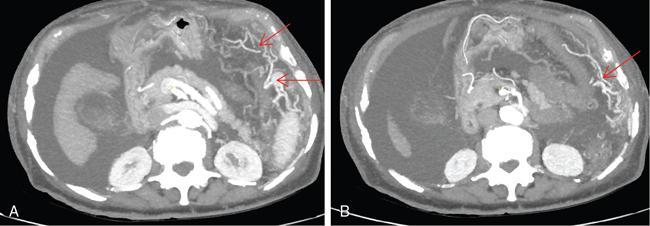

Shrinivas B. Desai, Ritu K. Kashikar, Aman Snehil, Ajay Jhaveri Cirrhosis is a late stage of irreversible scarring of the liver causing abnormality in liver structure and function. Multiple conditions and factors can cause repeated liver damage and scarring ultimately leading to cirrhosis. The most feared complication of liver cirrhosis is the development of hepatocellular carcinoma (HCC). Portal hypertension (PHT) is seen with a variety of conditions but cirrhosis happens to the most important cause. Imaging plays a vital role in noninvasive diagnosis and treatment planning of both cirrhosis and PHT. Liver imaging reporting and data system (LI-RADS) is a standardized reporting system assigning an observation risk of representing HCC. This chapter focuses on discussing aetiologies and imaging of PHT with a lucid review of L1-RADS 2018 version. The portal blood circulation is a unique circulatory circuit as it connects two capillary beds between the liver parenchyma at one end and the gastrointestinal tract and splenic parenchyma at the other end. The portal system ramifies in the liver and ultimately ends in the hepatic sinusoids from where the blood ultimately drains into the inferior vena cava (IVC). The portal vein (PV) originates from the capillary beds in the stomach, intestine and the spleen. The main PV is formed behind the neck of the pancreas by the confluence of the superior mesenteric vein (SMV) and splenic vein. It continues to the porta hepatis where it bifurcates into the left and right branches as it carries nutrient rich but oxygen poor blood to the liver (Fig. 9.9.1). The PV makes up for 75%–80% of the liver’s blood supply while the hepatic artery which arises from the celiac trunk makes up for the remaining 25%. A pathological increase in the portal venous pressure is referred to as PHT. PHT is most often a sequel of chronic parenchymal liver disease and leads to major life-threatening complications due to bleeding from the collateral circulation (most commonly oesophageal varices). Direct measurement of portal pressure (PP) is invasive and often not feasible in most patients and thus imaging plays an important role in the diagnosis of PHT and its complications. The normal portal venous pressure ranges between 5 and 10 mmHg, which is the equivalent of 7–14 cm H2O. The normal hepatic venous pressure gradient (HVPG) is the pressure gradient between the PV and the IVC, is typically 1–5 mmHg. Presence of PHT is indicated by a wedged hepatic venous pressure of more than 5 mmHg. Other definitions include a splenic pressure of more than 15 mmHg or an intraoperative PP of greater than 30 cm H2O. The complications of PHT are seen when HVPG is greater than 10 mmHg and hence this value defines clinically significant PHT. Variceal bleeding is seen with a pressure greater than 12 mmHg. In ideal conditions, the portal circuit is a high flow, low resistance circuit as it has to allow substantial flow rates of 700–1000 mL/min to the hepatic parenchyma from the gastrointestinal tract. Anatomical changes in the organization of the hepatic lobule can result in rise in the portal resistance. These can occur in the form of collagen deposition in the space of Disse, fibrotic scars formed due to regenerative nodule (RN) formation, loss of normal elasticity of the endothelium and distal venous thrombosis. Changes in splanchnic haemodynamics due to factors that increase splanchnic blood flow and increase in intrahepatic vascular resistance due to transformation of stellate cells into myofibroblasts also contribute to the increase in PP gradient. In Western countries, alcoholic cirrhosis and viral cirrhosis are the leading causes of PHT and oesophageal varices. The viral causes form majority of cases leading to cirrhosis and PHT in the Far East and Middle Eastern countries while Schistosomiasis remains an important cause in the African countries. Worldwide, nonalcoholic steatohepatitis (NASH) and hepatitis C are the emerging causes of chronic liver disease (CLD) and PHT. PHT can be classified as cirrhotic and noncirrhotic depending on whether it is associated with cirrhosis or not. This distinction is important as noncirrhotic causes like PV thrombosis are at high risk of development of bleeding but tend to have a better chance of surviving a variceal bleed than a patient with decompensated alcoholic cirrhosis due to preserved hepatic synthetic functions in the former. PHT can also be classified on the basis of the location of the pathology into prehepatic, hepatic and posthepatic causes. Hepatic causes can further be divided into presinusoidal, sinusoidal and postsinusoidal. The causes of portal hypertension have been denoted in Table 9.9.1. The direct measurement of the PP by measuring the HVPG is invasive, expensive not readily available in all patients. Thus, imaging plays an important role in the diagnosis of PHT. Various modalities are used for the imaging diagnosis of PHT. Ultrasonography (USG) and Doppler evaluation have the advantage of being inexpensive, readily available and bedside modality (Table 9.9.2). The role of ultrasound and Doppler in imaging of PHT is to: Grey scale imaging is useful in evaluating the splenoportal anatomy. The evaluation should begin with the liver morphology. Signs of cirrhosis like nodularity of the liver surface with relative atrophy of the right lobe and prominence of the left lobe and caudate should be looked for. Hepatic echotexture appears coarse and more echogenic (Table 9.9.3). Increase in portal venous diameter is a sign of PHT (Fig. 9.9.2). Portal venous diameter of more than 13 or 15 mm has low sensitivity for diagnosing PHT of only 40%–12.5%, respectively. Absolute measurement of the portal diameter as a sign of PHT is also fallacious as in presence of collateral circulation or hepatofugal flow; there may actually be a decrease in the PV diameter. Therefore, a more accurate sign is respiratory variation of PV diameter. An increase in PV diameter of less than 20% with deep inspiration has been reported to indicate PHT with a sensitivity of 80% and specificity of 100%. This has been reported to be an accurate indicator of cirrhosis. Hepatic vein straightness, uniformity of vein wall echogenicity and visualization of at least 1 cm segment of the hepatic vein are the parameters used for evaluation. Splenomegaly is defined as bipolar splenic diameter of greater than 12 cm or largest splenic cross-sectional area passing through the hilum of greater than 45 cm2, and occurs secondary to PHT (Fig. 9.9.3). A total of 65%–80% patients with cirrhosis have splenomegaly on ultrasound. Patients with cirrhosis due to viral hepatitis and primary biliary cirrhosis show splenomegaly more frequently than those with alcoholic cirrhosis. This is an accurate sign of PHT. USG is extremely sensitive with respect to detecting subclinical ascites. Perihepatic space is the most usual site of visualization of minimal ascites. In normal subjects, this ratio is approximately 0.07 and a value above 0.1 suggests the diagnosis of PHT with a 95% sensitivity and specificity. The normal spectral waveform of the hepatic artery is a low resistance flow pattern with forward flow in diastole and a resistivity index in the range of 0.5–0.7. In PHT, the resistivity index of the hepatic artery increases with high resistance flow pattern due to increased peripheral vascular resistance. Resistance index (RI) > 0.78 in the intrahepatic branches of the hepatic artery has been reported to have a sensitivity of 50% and a specificity of 100% for the detection of PHT (Fig. 9.9.11). Pulsatility index (PI) > 1.05 suggests severe PHT with a sensitivity of 86% and specificity of 88% (Fig. 9.9.11). Patency of hepatic veins should be evaluated to rule out Budd–Chiari syndrome as a cause of PHT. The normal hepatic venous waveform (HVW) reflects right atrial activity and this results in a triphasic waveform with one positive and two negative waves. In PHT, this waveform becomes monophasic or biphasic. A monophasic HVW has a sensitivity and specificity of 74% and 95%, respectively, in the diagnosis of severe PHT (Fig. 9.9.12). Dilatation of the splanchnic veins – the SMV and the splenic vein – more than 11 mm are suggestive of PHT with a sensitivity and specificity of 72% and 100%, respectively. A reduction in the respiratory variation of the splenic vein and SMV to less than 40% had a sensitivity and specificity of 79.7% and 100%, respectively, for the diagnosis of PHT (Fig. 9.9.13). The splenic artery reveals an increase in the resistivity index and an RI of >0.63 and a PI of >1 have a sensitivity and specificity of 84.6% and 70.4% for the diagnosis of PHT. Presence of portosystemic collaterals like patent paraumbilical vein, dilated left gastric and short gastric veins are 100% specific sign for PHT (Figs. 9.9.14–9.9.16). Recanalization of the paraumbilical vein, known as the Cruveilhier–Baumgarten syndrome is observed in 43% of patients with PHT, and this is the easiest collateral to assess during the US examination. Various portosystemic collaterals that occur in PHT have been discussed in details in subsection on CT findings in PHT. No Doppler parameter is considered reliable enough to measure PP with sufficient accuracy for use in clinical practice. Oesophageal varices are often present in patients with portosystemic collaterals. Appearance or increase in number of collaterals along with splenomegaly has a high association with variceal formation and growth. USG helps in diagnosis of prehepatic causes like portal stenosis or thrombosis by demonstrating the patency and morphology of the splenoportal system. Arteriovenous fistulae and tumours causing vascular thrombosis as aetiology can be readily detected. USG helps in diagnosis of features of cirrhosis and thus helps differentiate noncirrhotic causes of PHT. USG allows diagnosis of fatty liver disease, which is an emerging cause of cirrhosis. Among the posthepatic causes, USG aids in establishing the diagnosis of Budd–Chiari syndrome by demonstrating the patency and morphology of the IVC and hepatic veins. Owing to the inability of CT to detect flow direction, portal flow rates or pressure gradients, CT is not the primary modality in diagnosis of PHT. Similar to USG dilatation of portosystemic system is a feature of PHT (Fig. 9.9.17). Changes in cirrhosis if present can be seen in the form of surface nodularity, nodules and fibrous septae. CT plays an important role in diagnosis of portal venous thrombosis and evaluating its extent. An acute thrombus is seen as a hypodense filling defect in the vessel causing distension of the venous lumen. Surrounding fat stranding can be seen. A chronic thrombus appears as an eccentric filling defect usually along the wall and is often associated with decrease in vessel diameter. Calcification may be seen in chronic thrombi. Multidetector computed tomography (MDCT) is a useful tool to evaluate portosystemic collateral circulation and recognize complications of PHT. 3D angiography can help understand portal venous and complex variceal anatomy and plan treatment. The various portosystemic collaterals are discussed below. They can be classified into those draining into superior vena cava (SVC) and those draining into the IVC. Magnetic resonance imaging (MRI) is a noninvasive modality used in the evaluation of PHT without the use of ionising radiation. It provides evaluation of parenchymal abnormalities, collaterals and characterization of tumours (Fig. 9.9.28). Spin echo sequences allow characterization of liver masses and liver parenchyma. Loss of flow void allows for detection of thrombosis. Time-of-flight (TOF) angiography is useful in assessing the portal venous system and allows for successful detection of PV thrombosis. The disadvantages of TOF are motion artefacts caused by breathing, long acquisition times and incomplete coverage of the portal venous system. Novel imaging techniques include phase contrast, T1 mapping and magnetic resonance elastography (MRE). The advantage of phase contrast over TOF imaging is that phase contrast imaging acquires information regarding the flow direction in addition to the information regarding the flow velocity. On-phase contrast images signal within vessel is hyperintense when flow is cranial and hypointense when flow is caudal. Look-Locker imaging technique using gradient echo (GRE) MRI sequences with inversion recovery pulse is used to quantify fibrosis by measuring precontrast T1 relaxation times. Interventions in PHT can be aimed at diagnosis or more commonly at management of complications of PHT. HVPG measurement, which is the gold standard for the diagnosis of PHT, can be achieved through cannulation of the PV. Transjugular hepatic biopsy is another diagnostic invasive technique that also allows indirect measurement of PP. Disadvantages include deterioration of hepatic function caused by diversion of portal venous blood flow and shunt dysfunction. TIPSS is contraindicated in patients with congestive heart failure, severe pulmonary hypertension, severe tricuspid regurgitation and hepatic failure. In this technique, a catheter is advanced from the femoral vein into the outlet of the gastrorenal, usually in the region of the left renal vein. The shunt is then occluded with a balloon and sclerosant is injected retrograde to occlude the gastric varices. Histological development of RNs surrounded by fibrous septae in response to chronic liver injury, progressing PHT and end-stage liver disease is termed as cirrhosis. Although initially considered an end-stage phenomenon in CLD, recent evidence suggests that the histological fibrosis can be reversible in early stages with the initiation of specific therapies, for example, in viral cirrhosis with the initiation of antiviral therapy. The one-year mortality rate in cirrhosis varies widely from 1% to 57% depending on the occurrence of complications. Cirrhosis can have a wide variety of causes ranging from congenital to acquired and infectious to noninfectious. It is also a major aetiologic risk factor for the development of HCC. Imaging plays an important role in aetiologic diagnosis of this diverse entity as well as in the diagnosis and management of its complication and surveillance for oncological transformation.

CT scan